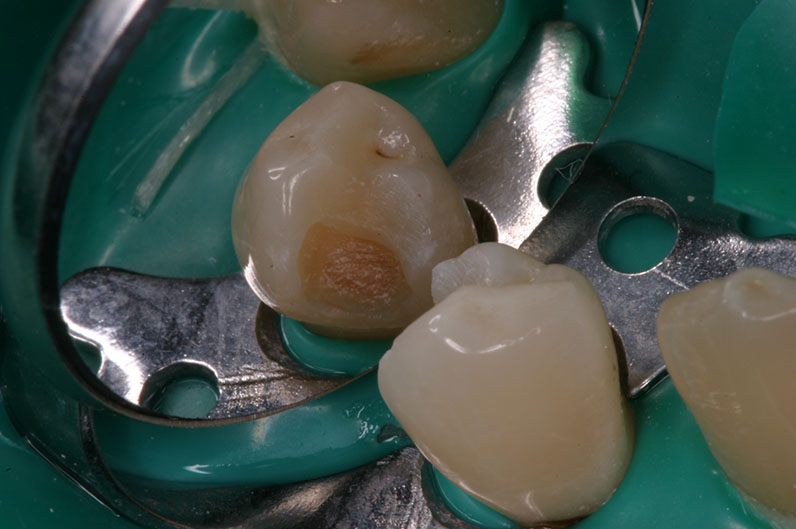

След екскавиране